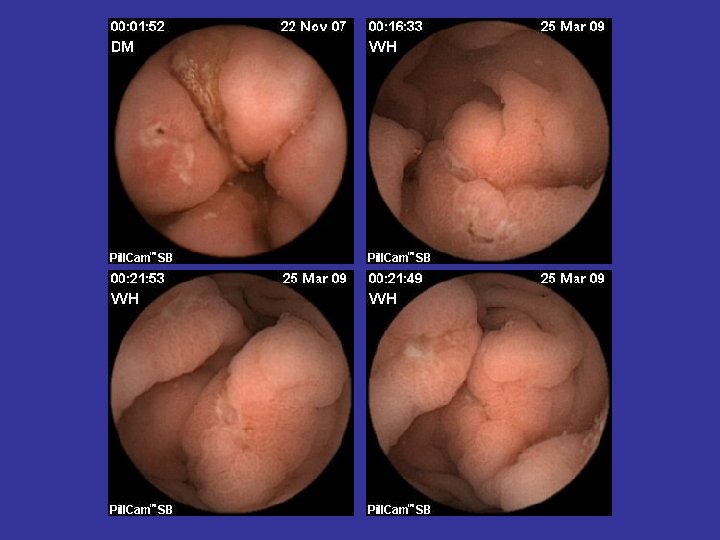

Tipuri de leziuni depistate in BC • • Eroziuni Edem mucosal Congestie parcelara Ulceratii aftoide; Ulcere liniare/ neregulate/ confluente; Pseudopolipi inflamatori; Stenoze inflamatorii;